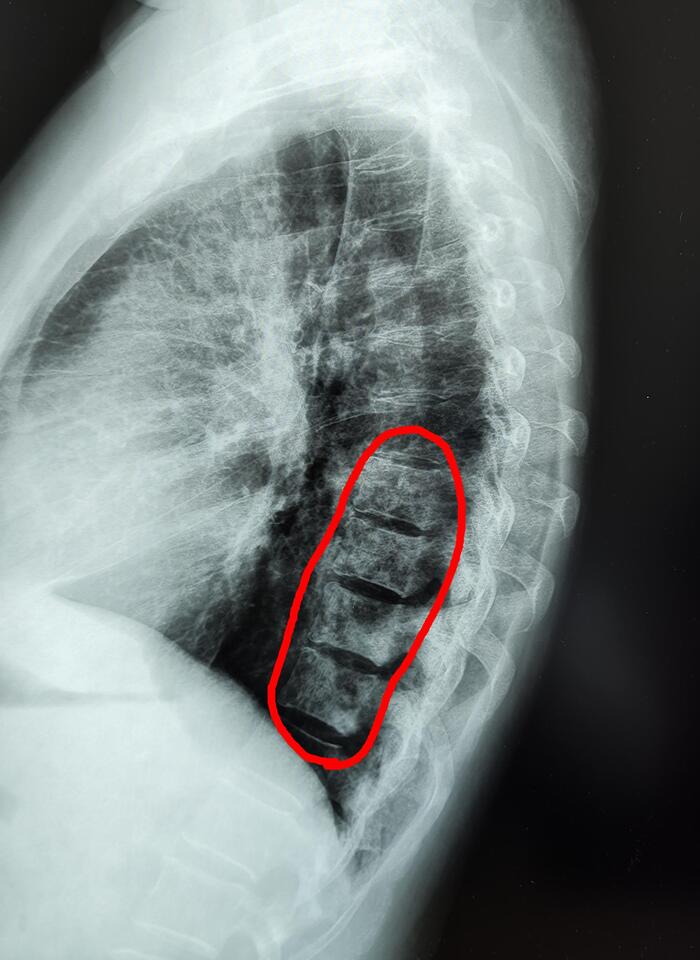

Порок развития протекает бессимптомно. Его диагностируют на рентгенограммах, флюорограммах в прямой/задней проекциях.